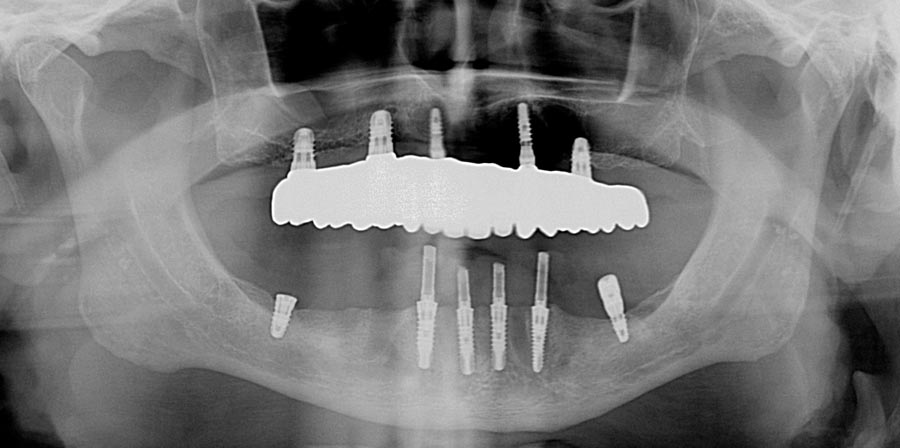

Occlusal (mirror) view of the upper implants. This patient had good bone in these five areas. If the bone was better we would have added a sixth implant.